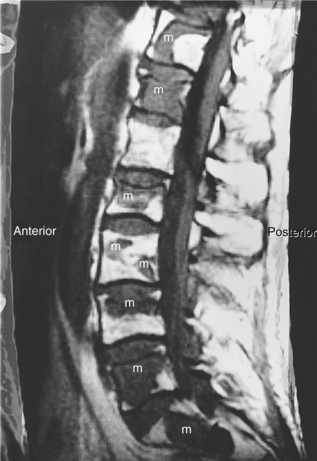

The early effects of a CNS tumor are related to mechanical displacement of brain or spinal cord tissue, or a mild block in cerebrospinal fluid (CSF) circulation, causing increased intracranial pressure (ICP). As a tumor grows, compression or destruction of local brain or nerve tissue may occur, resulting in specific neurologic deficits. Symptoms of brain tumors may range from minimal, such as mild lethargy, to marked, such as seizures, blindness, and paralysis, as the tumor progresses. Likewise, symptoms of spinal cord tumors may range from mild to severe and include pain, sensory impairments, weakness, and paralysis. Although primary CNS tumors typically do not metastasize outside the CNS because of the lack of a CNS lymphatic system to transport cancer cells, these cells may infrequently travel through the CSF to the spinal cord as “drop metastasis” and cause spinal cord complications.

Because the clinical presentation, treatment, and prognosis are heavily dependent on the location of involvement and whether the tumor is primary or metastatic, this discussion is divided into four parts: (1) primary brain tumors, (2) primary intraspinal tumors, (3) metastatic tumors, and (4) childhood brain tumors.

Clinical Manifestations.: Medulloblastoma often develops in the cerebellar vermis and is very aggressive in younger children. Because of its proximity to the fourth ventricle, early development of hydrocephalus is common, along with other signs of cerebellar dysfunction, such as ataxia. Medulloblastomas tend to metastasize through CSF pathways, more predominantly into the spine but also into the supratentorial compartment.

Pathogenesis.: Medulloblastoma is a rapidly growing malignant tumor. The cell of origin is unknown, but it is presumed to arise from the embryonal external granular layer of the cerebellum. It is considered to belong to a group of tumors known as primitive neuroectodermal tumors (PNETs). It characteristically metastasizes to the surface of the remaining CNS via the subarachnoid spaces. Grossly it is red and soft and is composed of many closely packed cells, with oval nuclei and many mitoses. Pseudorosette formations are common. It is highly vascular, containing numerous small blood vessels.126